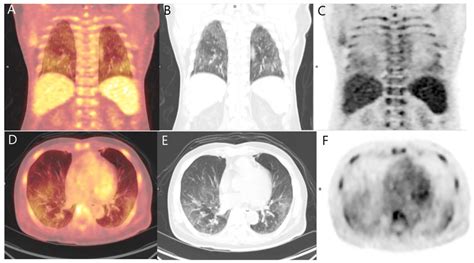

Metastatic Pulmonary Calcification Detected on 18F-FDG PET/CT and 99mTc ...